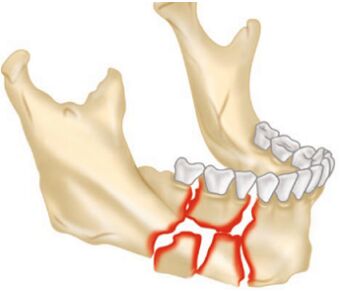

42.圖示之下顎骨骨折,單純使用骨內固定時的考量,下列敘述何者錯誤? (A)必須考慮以load bearing osteosynthesis的概念來進行固定 (B)可以使用數片2.0 mm的迷你骨板進行骨塊的復位及固定 (C)進行骨塊固定前需先確認咬合 (D)在骨體中間及靠牙齒區域不合適使用雙皮質骨釘(bicortical screws)進行固定

45.對於附圖的骨折說明,何者最適當?①compound fracture ②complex fracture ③simple fracture (A)僅① (B)①② (C)①③ (D)②③